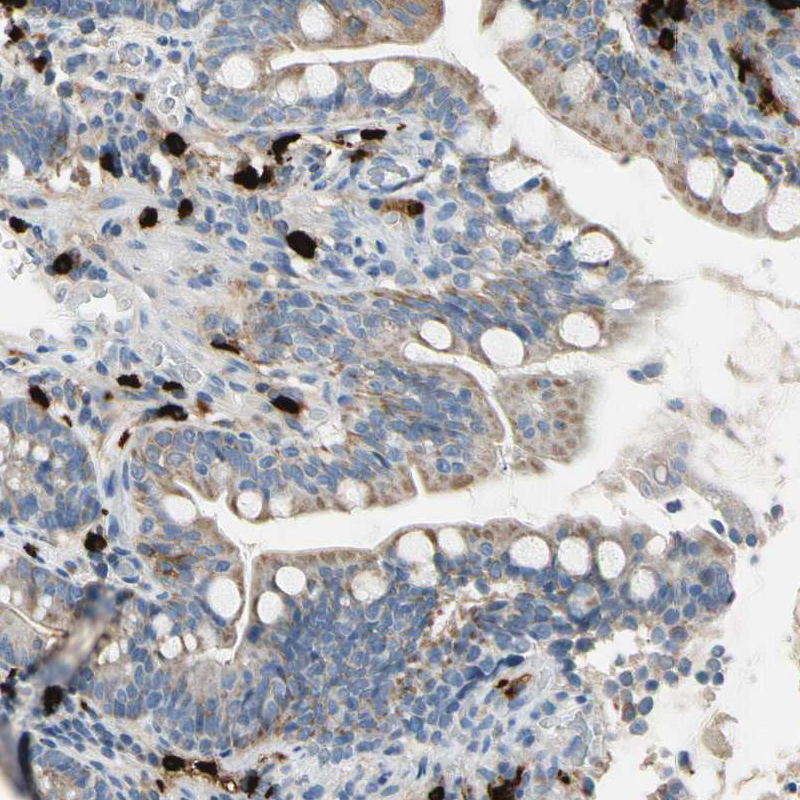

Immunohistochemistry analysis in human cervix, uterine and skeletal muscle tissues using HPA008689 antibody. Corresponding CPA3 RNA-seq data are presented for the same tissues.